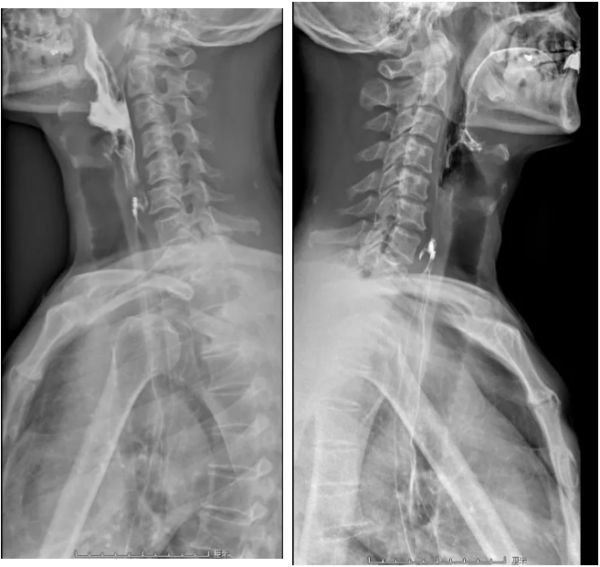

在医院的消化内科就诊后,医生为赵先生安排了钡餐检查,结果真发现了问题。在赵先生的食管上段发现一个憩室,直径约2.5cm。

患者检查结果